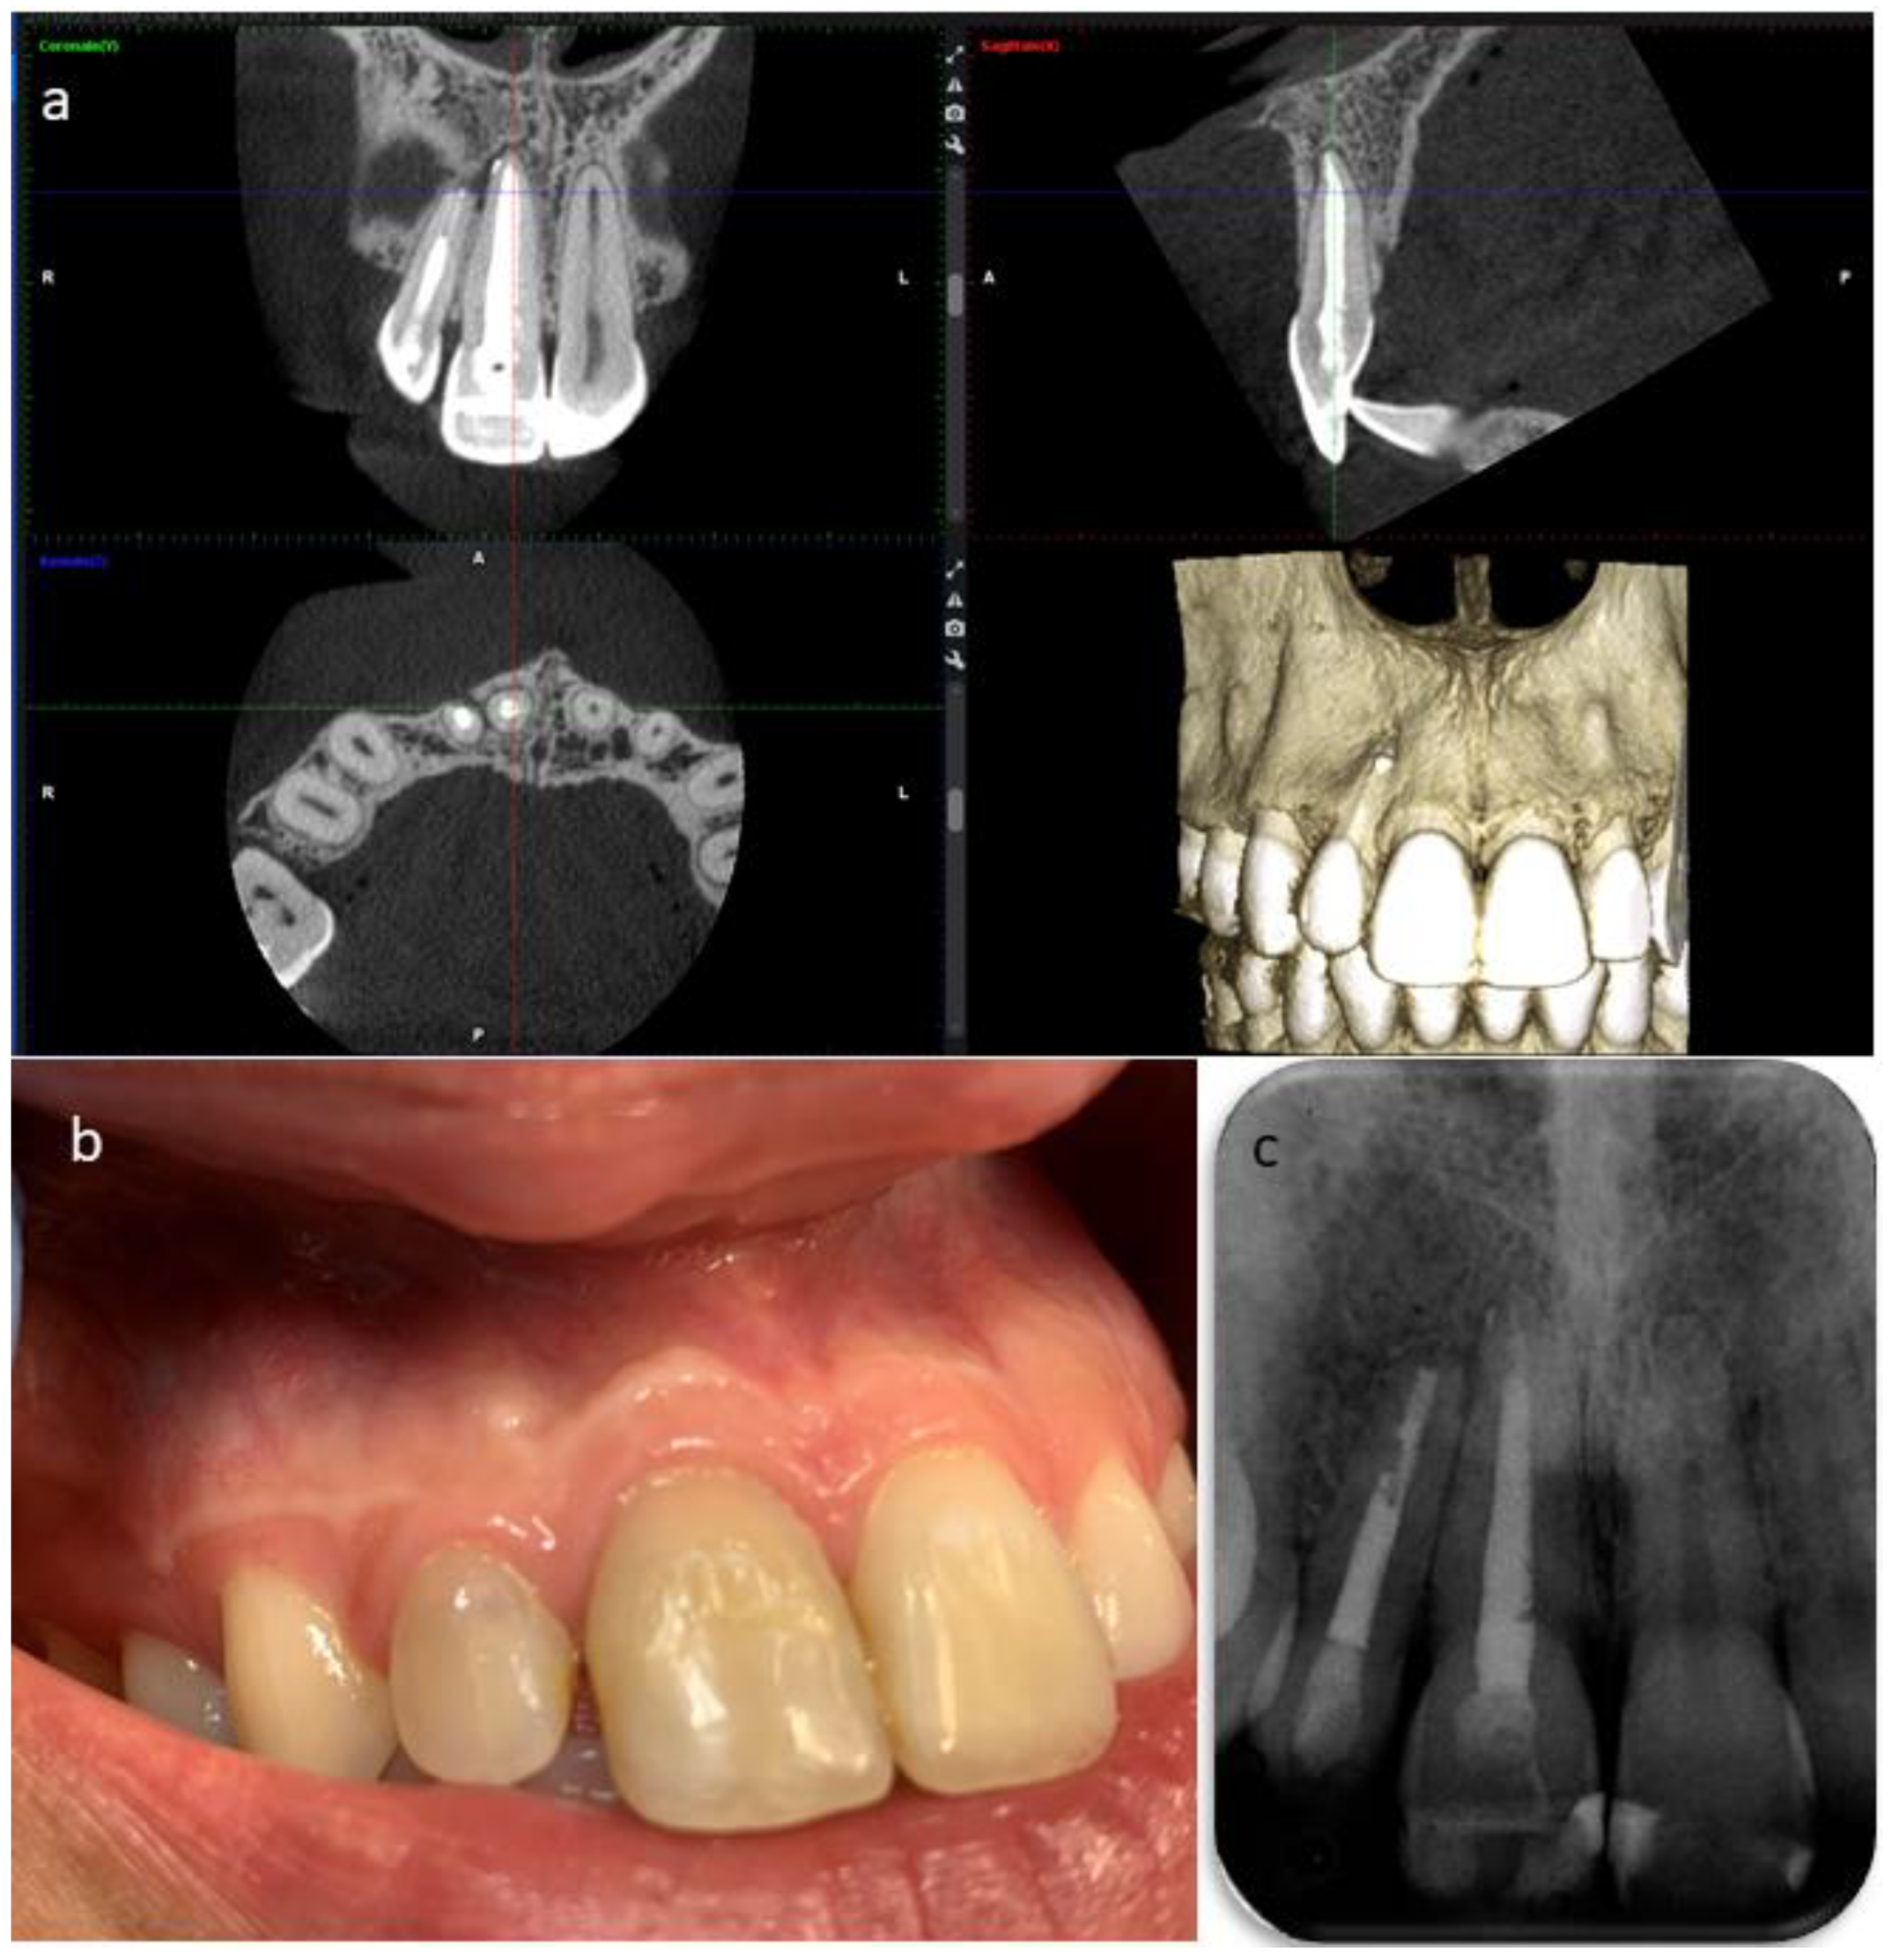

Dentistry Journal Free Full Text Management Of The Sequelae Of A Sport Related Traumatic Dental Injury Using Ultrasound Examination In The Diagnosis And Follow Up Html